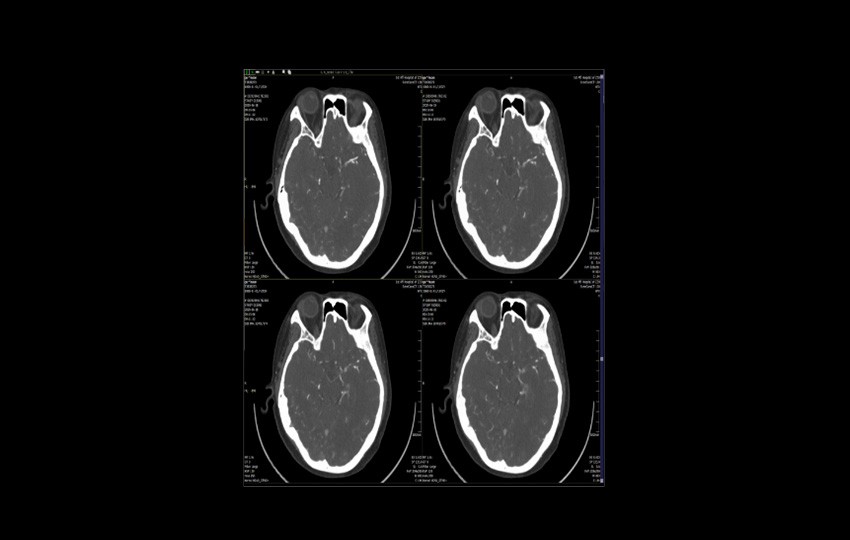

Caso 1-1<br>TAC de la artería cerebral

TAC de la artería cerebral